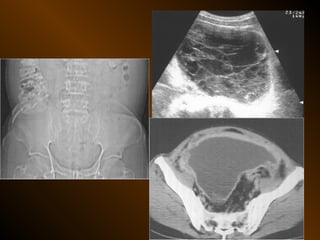

TỤ DỊCH TRONG PHÚC MẠC

• X QUANG QUY ƯỚC

– Trong tiểu khung

– Dọc hai bên hông

– Giữa bụng

• SIÊU ÂM

– Phản âm trống, chuyển dịch

– Lượng ít

– Bản chất dịch

• X QUANG CẮT LỚP ĐIỆN TOÁN

– Mật độ

– Vị trí

– Nguyên nhân

TỤ DỊCH KHU TRÚ

– Tụ dịch ? – khối u ?

– Phản âm, chất chứa, vỏ bọc ?

– Mật độ, bắt cản quang ?